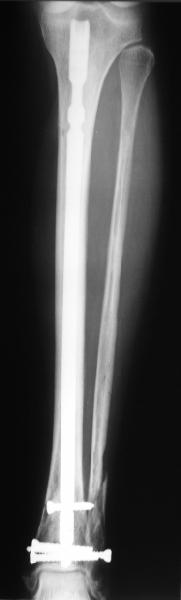

In delayed cases acute length restoration performed only in the tibia may leave the fibula shortened thus change the mortise. So it is reasonable to restore length of both bones simultaneously by distractor and fix the fibula not with open reduction and plating but just by a single perQ screw. Example attached.